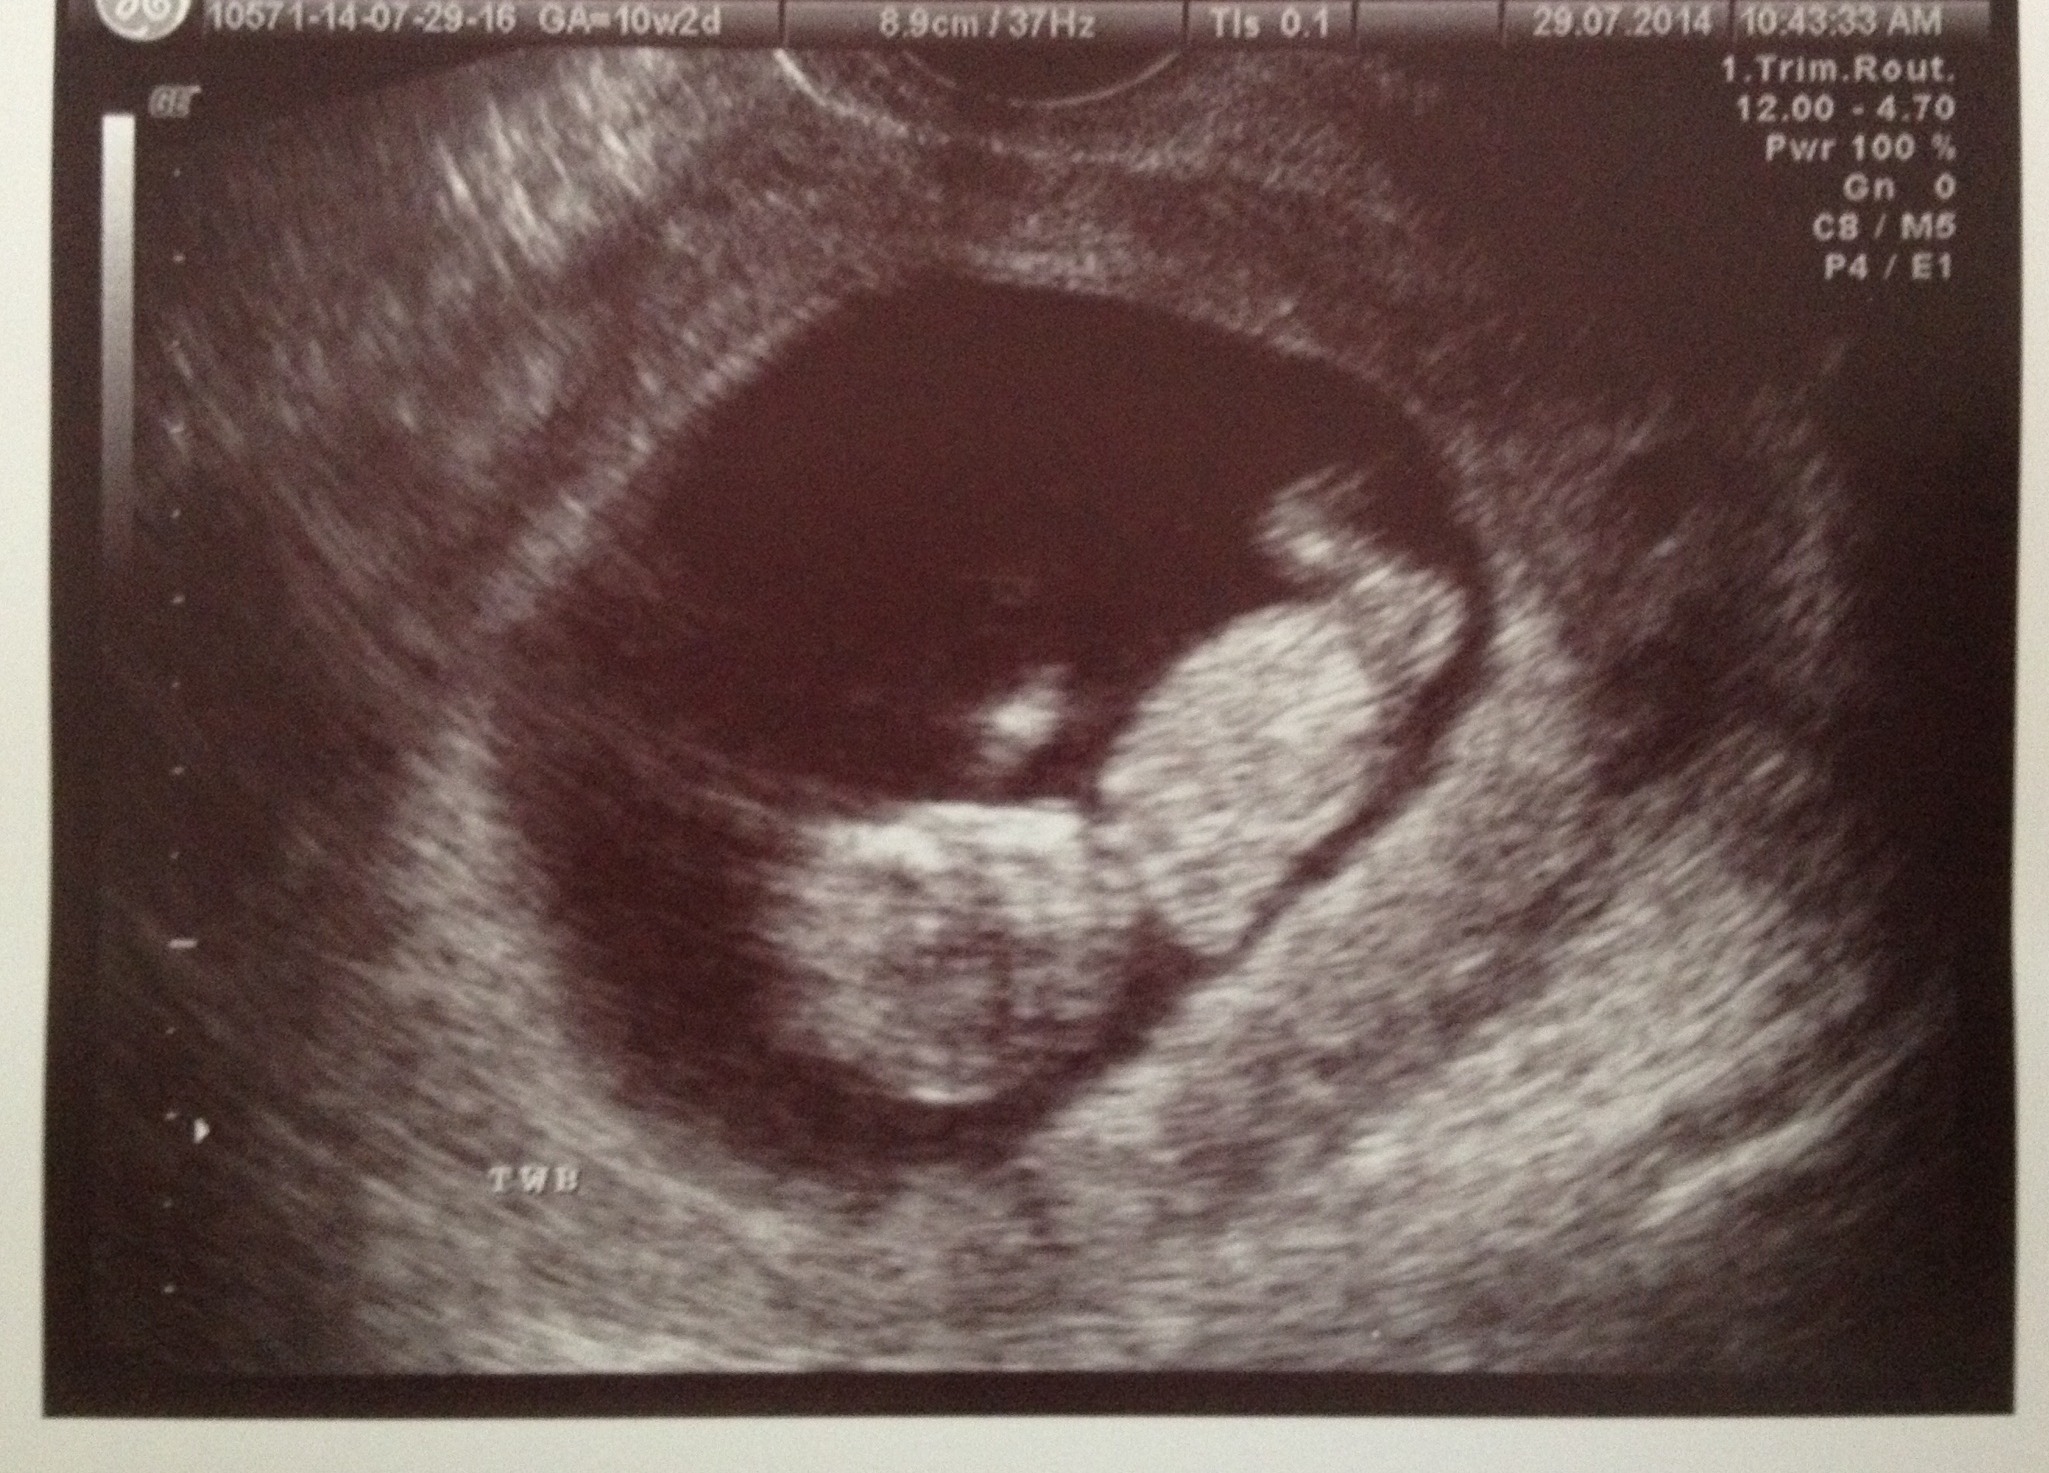

Had my last real appt with the RE this morning! (Although I may go back if my OB has trouble scheduling my NT scan). It was a seriously amazing appt! Baby A was dancing up a storm, wiggling around, being all cute and baby like! Baby B was snoozing away, sucking it's thumb. What a difference from a couple of week ago, my gummy bears now look like babies!!! And while I'm AWing, here they are!